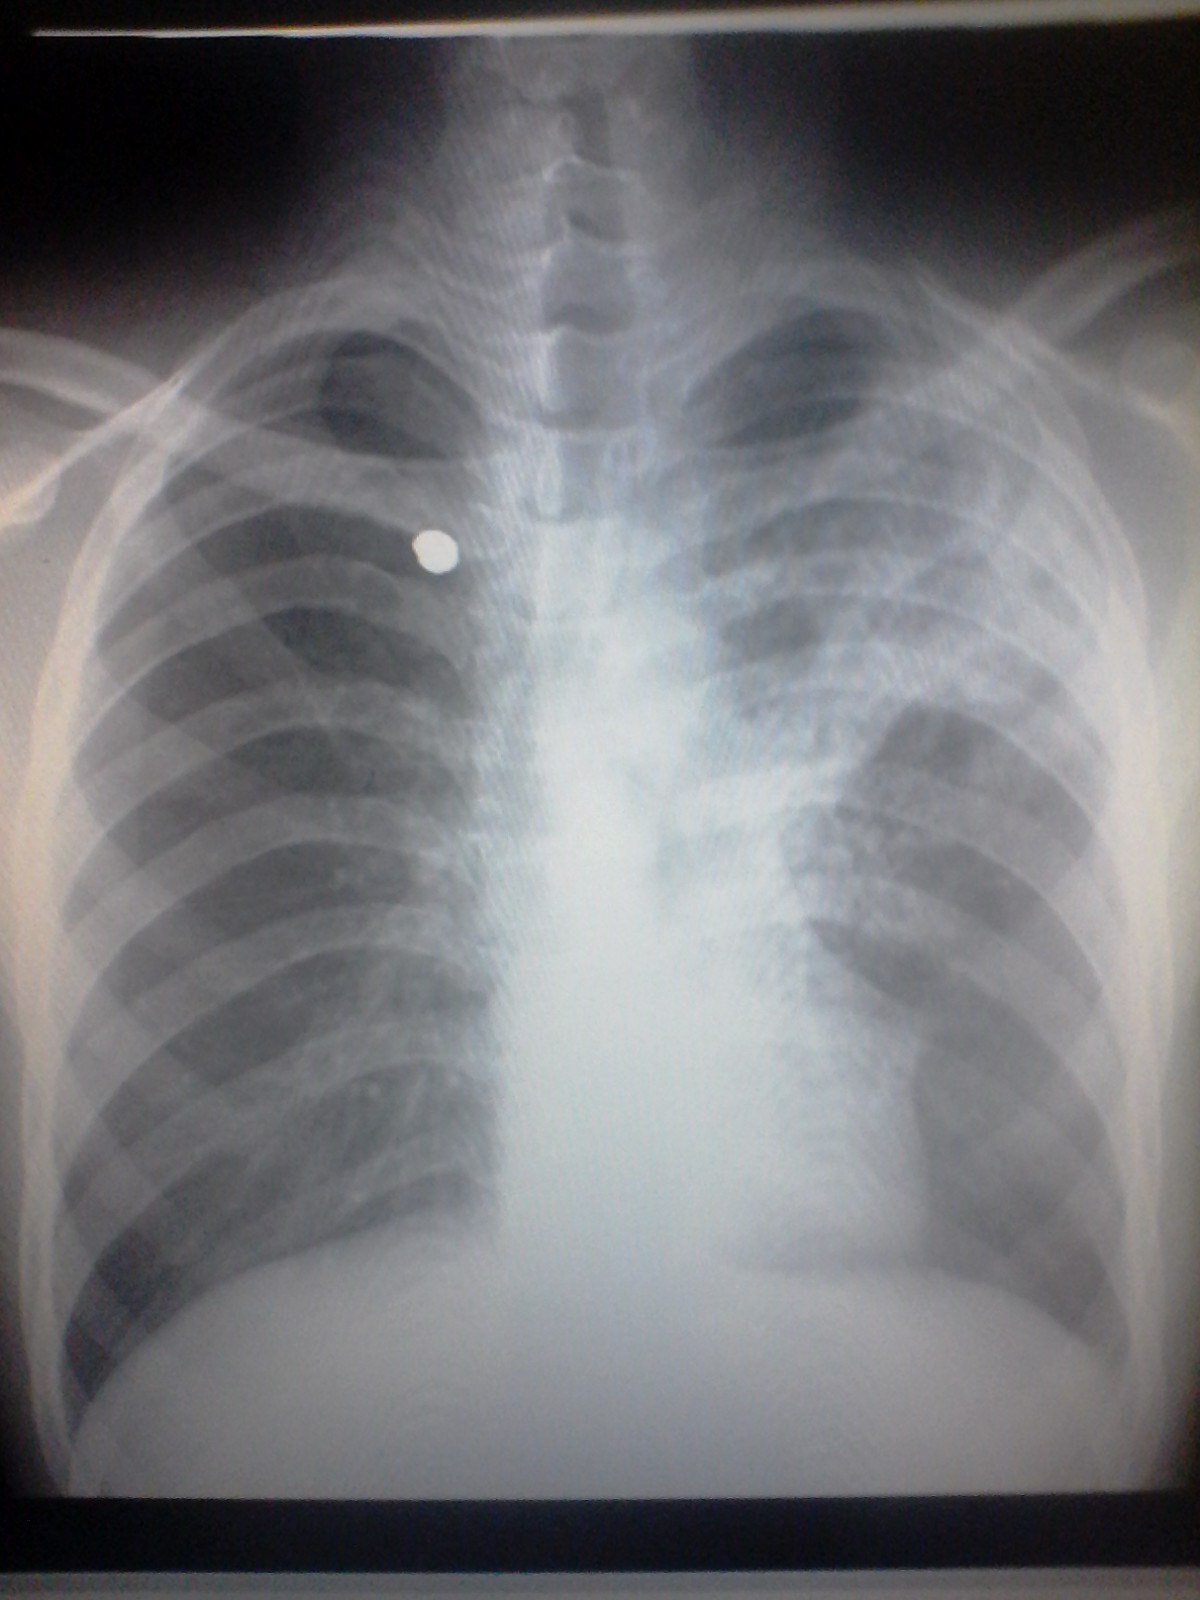

Diagnostico medico por Imagen